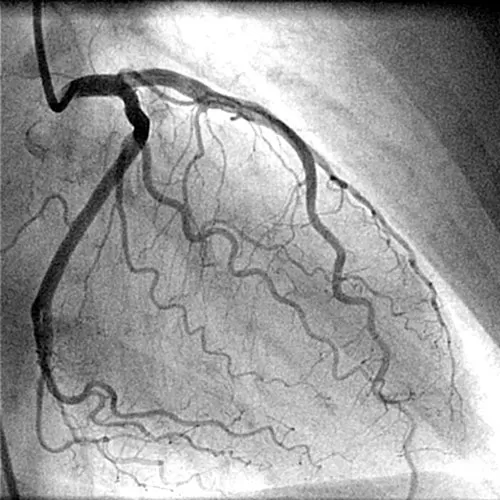

Коронарография

Наиболее точный рентгеноконтрастный метод исследования, позволяющий достоверно произвести диагностику ишемической болезни сердца (ИБС) и решить вопрос о выборе и объеме проведения в дальнейшем таких лечебных процедур, как баллонная ангиопластика, стентирование, аортокоронарное шунтирование (АКШ).

Исследование проводится под местной анестезией, пациент находится в сознании. Катетр вводится через прокол в бедренной артерии и под рентгенологическим контролем продвигается к коронарным артериям. Через катетер вводится контрастное вещество, которое, заполняя сосуды, позволяет визуализировать просвет артерий.

В процессе исследования выполняется серия снимков в разных проекциях и по ним оценивается проходимость артерий.